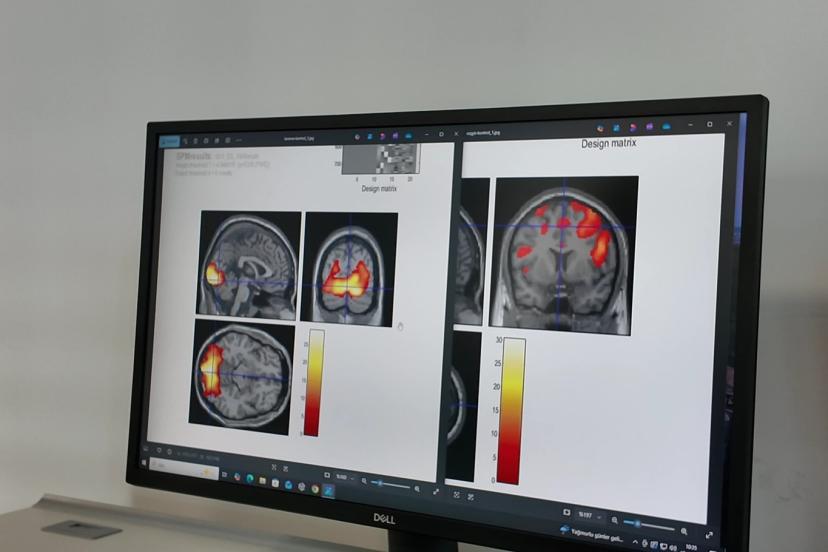

Çalışmada, migrenli bireylerin tekrarlayan görsel uyaranlara karşı alışma (habitüasyon) geliştiremediği ve bu uyaranların beyin tarafından sürekli “önemli” olarak kodlandığı belirlendi.

“Normal insan beyninde tekrarlayan uyarı geldiğinde beyin buna verdiği tepkiyi azaltıyor. Ama migrenli beyin aksine tepkiyi giderek arttırmaya başlıyor.” diyen Prof. Dr. Belen, bu artışın, görsel işlemenin yapıldığı beynin arka kısmında değil aksine beynin en ön kısmında bulunan ve üst düzey kontrol merkezi olan orbitofrontal bölgede gerçekleşmesinin son derece önemli olduğunu ifade etti. Belen, “Burası görmenin üst düzey kontrol merkezi ve aynı zamanda da gelen uyarıya zararlı, faydalı ya da duygusal bir değer biçen yer.” dedi.

Doktora sonrası araştırmacı Dr. İlkem Güzel de “Alt düzey görsel işlemleme bölgelerinin doğrudan ağrı bölgesiyle ilişki halinde olduğunu tespit ettik. Bu tespit bize migren hastalarında ışıktan rahatsız olma durumunu açıklama fırsatı sundu.” dedi.